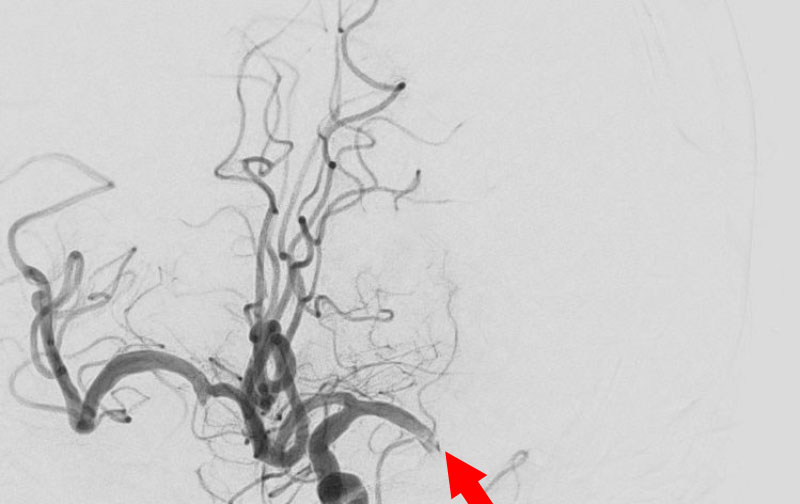

'25年11月

くも膜下出血

破裂性内頚動脈解離

40代

救急外来

No.1594 手術前

No.1594 手術中

No.1594 手術後